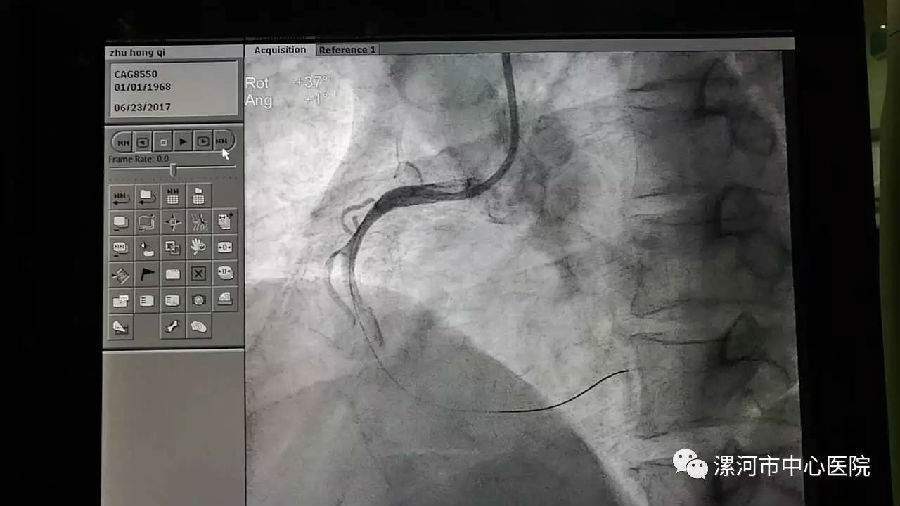

下午1时30分,院工会主席、胸痛中心领衔专家刘东亮带领心内科二病区主任董艳彩、副主任医师彭庚、主治医师王前胜把患者送进介入导管室进行冠状动脉造影术。

造影显示,患者右冠脉完全闭塞且血栓较多,考虑到患者血管较粗,血栓负荷较重,专家团队用血栓抽吸导管行冠状动脉内血栓抽吸术和冠状动脉内球囊扩张术进行血管开通。